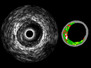

We’re taught from an early age that our teeth are important and that we should look after them. Sometimes, however, something goes wrong, and we lose teeth. How can they be replaced? What about growing some new ones? Researchers have successfully grown tooth-like structures (left) in ‘artificial gums’ (right) using induced pluripotent stem cells (iPSCs) – mature cells that have been ‘reprogrammed’ to become stem cells that can then be used to generate new tissues. What’s more, these iPSCs came from humans, and so new teeth could potentially be grown from the cells of the person who needs them. In fact the source of these particular iPSCs was urine. They’re derived from sloughed bladder cells – a normal component of our everyday waste disposal – which puts a whole new slant on the wisdom of recycling.